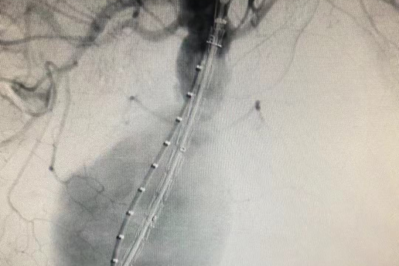

临危救险!微创介入治疗腹中精准「拆弹」